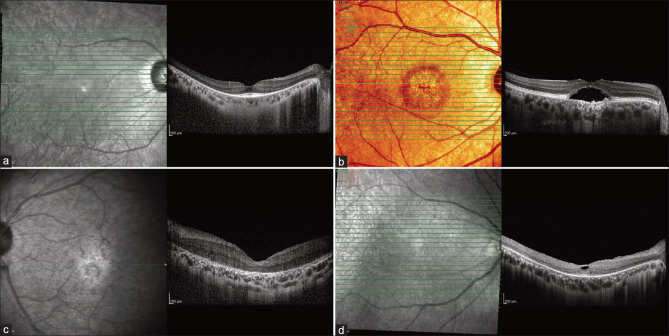

遗传性视网膜变性(IRD)是一种异质性的遗传性疾病,具有不同的发病和严重程度,在大多数情况下,视力丧失是一个共同的终点。已有超过50种不同的IRD表型和超过280种致病基因被描述。建立IRD患者的临床表型尤其具有挑战性,因为即使在具有相似基因型的患者中也存在临床差异。临床表型为了解疾病进展和告知后续遗传调查提供了基础。需要为IRD病例建立明确的临床表型,以证实从外显子组和基因组测序中获得的数据,这些数据通常会产生与IRD相关的基因的大量变异。在当前的工作中,我们回顾了当代视网膜成像方式的使用,包括超宽视场和自身荧光成像,光学相干断层扫描和多光谱成像,在诊断视网膜视网膜病变中的应用。

Inherited retinal degeneration (IRD) is a heterogeneous group of genetic disorders of variable onset and severity, with vision loss being a common endpoint in most cases. More than 50 distinct IRD phenotypes and over 280 causative genes have been described. Establishing a clinical phenotype for patients with IRD is particularly challenging due to clinical variability even among patients with similar genotypes. Clinical phenotyping provides a foundation for understanding disease progression and informing subsequent genetic investigations. Establishing a clear clinical phenotype for IRD cases is required to corroborate the data obtained from exome and genome sequencing, which often yields numerous variants in genes associated with IRD. In the current work, we review the use of contemporary retinal imaging modalities, including ultra-widefield and autofluorescence imaging, optical coherence tomography, and multispectral imaging, in the diagnosis of IRD.